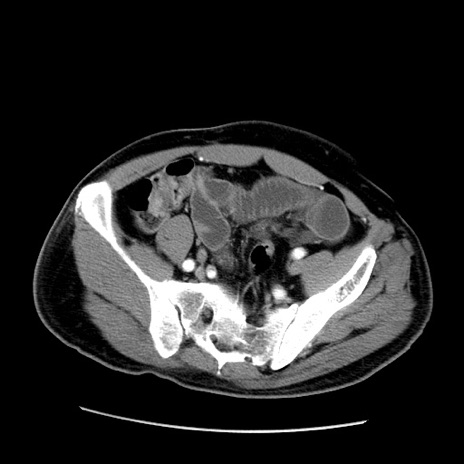

症例22(横断像)

【症例】50歳代男性

【主訴】腹痛

【現病歴】AVMからの被殻出血のため回復期リハ病棟入院中。 本日午後3時頃急に下腹部痛が出現した。

【既往歴】AVM、被殻出血、虫垂炎、高血圧

【身体所見】意識晴明、左半身不全麻痺、会話の理解は良好、36.5°C、腹部:膨隆、全体に板状硬、下腹部正中に圧痛点あり、反跳痛-、筋性防御不明、右下腹部にope scar

【データ】WBC 9400、CRP 0.06